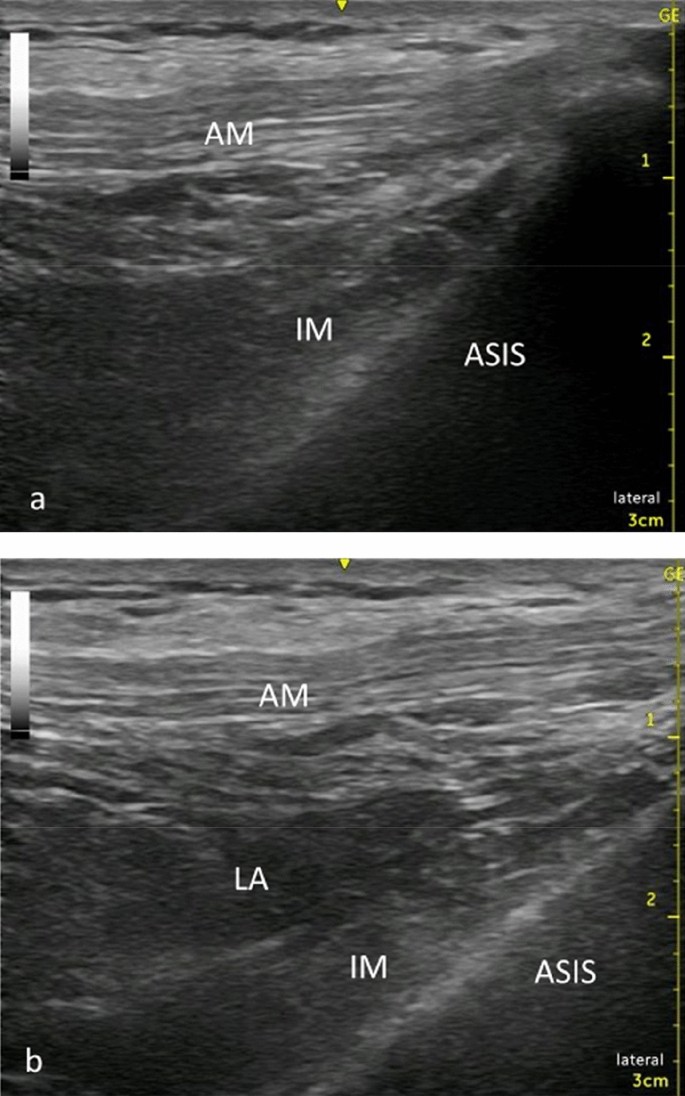

The supra-inguinal FICB was performed using a sterile technique with the patient in the supine position. Patients received a FICB under ultrasound guidance using Venue40 (GE Healthcare, Tokyo, Japan) ultrasound unit. After placing a linear probe (5–13 MHz) parallel to the inguinal ligament on the inguinal crease, we found the femoral artery and femoral nerve. From this view, we rotated the probe 90°, making the probe parallel to the vertebral axis. The probe then moved laterally until the anterior superior iliac spine was imaged, and the iliac muscle and abdominal muscles were identified. The medial end of the transducer was rotated to the umbilicus. In this position, a 60-mm needle (23G, Cathelin needle; Terumo Corp, Tokyo, Japan) was introduced at the transducer caudal edge. Using the in-plane approach, the fascia iliaca was penetrated and hydro dissected, separating the fascia iliaca from the iliac muscle. The predetermined volume of 0.25% ropivacaine was injected (Fig. 1).